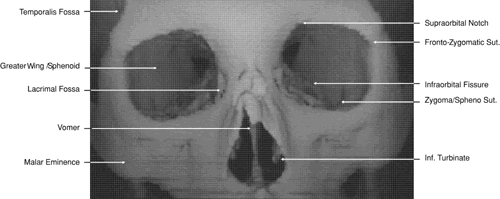

The globe is shown in Figure 12. The orbit and periorbital structures are shown in Figures 13 through 16, and the optic canal is shown in Figures 17 through 26. The cavernous sinus and optic chiasm are shown in Figures 27 and 28, and the posterior visual pathway and cranial nerves are shown in Figures 29 through 33.

Fig. 13. Three-dimensional reconstruction of orbit and infraorbital structures (Water's view).

Fig. 14. Three-dimensional reconstruction of orbit (anterior view).

Fig. 15. Three-dimensional reconstruction of orbit and cranial cavity (superior view).

Fig. 16. Three-dimensional bone reconstruction of cranial cavity structures (view from posterior cranial fossa).

ORBIT AND PERIORBITAL STRUCTURES

The bony orbital and periorbital anatomy is best visualized with CT, whereas the soft tissue anatomy can be visualized with either CT or MRI. The orbital cavities are roughly shaped like quadrilateral pyramids parallel to each other medially and lying on one side with their apex facing posteriorly. The widest portion of the orbit is approximately 1.5 cm posterior to the orbital rim (see Fig. 2). On average the adult orbit is 40 to 45 mm deep, with the anterior orbit measuring 40 mm wide and 35 mm high. The interorbital distance in the normal adult is 25 mm. In contrast, the newborn orbit is more rounded, with a width and height of 27 mm, and the orbit of a 7-year-old measures 28 mm high and 33 mm wide.48 The orbital volume is approximately 30 mL, in comparison to the globe, whose diameter of24 mm gives it a volume of 6.5 to 7.0 mL.